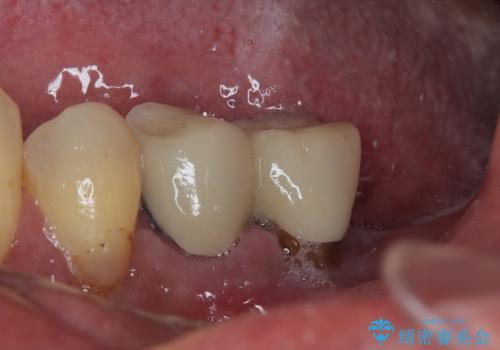

骨吸収が甚大な後方は3ヶ月ほど待機して、手前は抜歯即時埋入により、短期間インプラント補綴治療を行うこととしました。

骨吸収が大きかったため、待機期間を必要としましたが、外科処置は初診時の抜歯も含めて3回に抑えることができ、半年の短期間で治療を終えることができました。